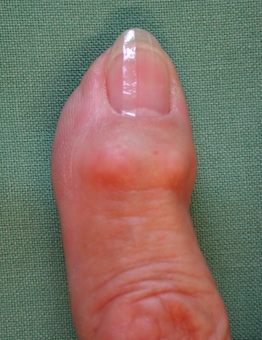

Als Folge einer Arthrose kommt es zu Schmerzen im Bereich der Gelenke in Ruhe und bei Belastung sowie zu Schwellneigung. Am betroffenen Gelenk bilden sich knöcherne Ausziehungen, die außen als Knoten sindbar sind. Streckseitig über dem Endgelenk können sich Mukoidzysten bilden als Ausdruck der Arthrose, die durch den Druck auch Eindellungen im Nagel verursachen können. Mit der Zeit kommt es zur zunehmenden Funktionseinschränkung; gelegentlich kommt es auch zu einer Achsabweichung. Lange Zeit sind die Schmerzen wenig störend, nehmen mit zunehmendem Verschleiß jedoch zu, so dass Schmerzmedikamente keine Linderung mehr bringen. Eine Besserung durch Schonung oder Ruhigstellung ist auf Dauer nicht erfolgversprechend.